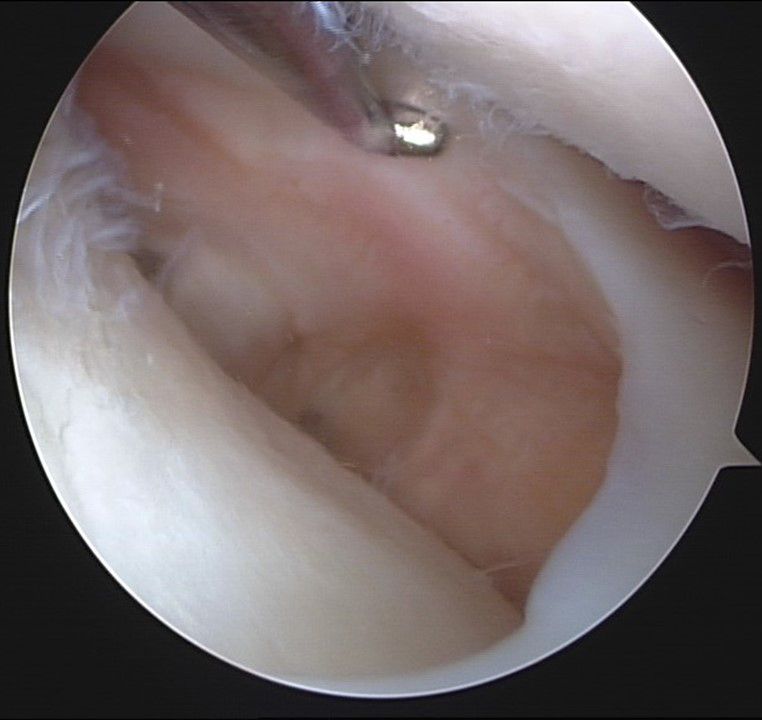

Fig 25 and 26 - Arthroscopic ( 30° ) and schematic view of the fixed graft